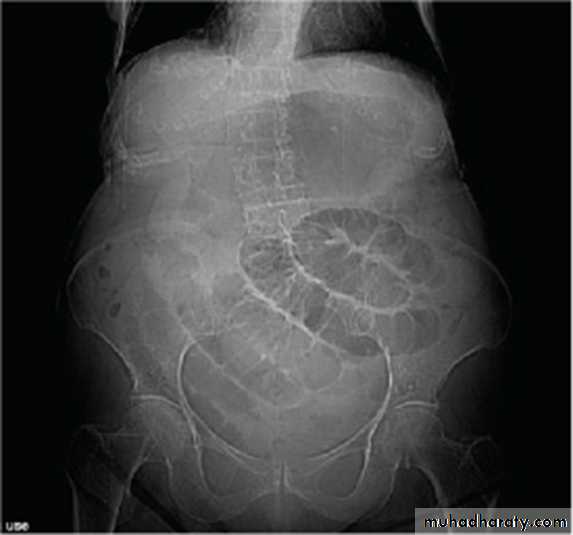

Obturator Hernia

9 : 1 female to male ratio

Typical patient is > 70 yrs of age

Multiparous women

Up to 20% bilateral

Concurrent Femoral hernias common

CLINICAL PRESENTATION

• Intestinal obstruction• most common presentation (80%)

• Up to 70% mortality with strangulation

• Overall mortality 25%

• Correct preoperative diagnosis in 20% to 38% of patients